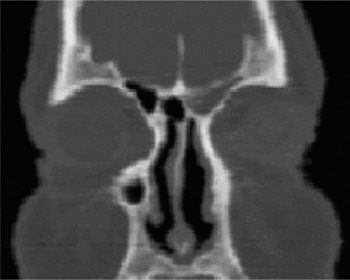

When the fluid leaks from the nose, this condition is called csf rhinorrhea. How do i know if my nasal fluid is csf To diagnose a cerebrospinal fluid (csf) leak, your doctor may need to collect samples of your nasal discharge to differentiate between csf and regular nasal mucus Various symptoms and tests, including imaging studies, can help identify a csf leak

Most csf leaks heal on their own, but some need medical care Cranial csf leak or csf rhinorrhea this is a condition when csf or cerebrospinal fluid leaks through the nasal cavity causing clear runny nose with no overt signs of allergy or infection A healthcare provider can diagnose csf based on symptoms, fluid composition, and imaging tests.

Learn about the diagnosis and treatment options for csf leak. A leak that occurs at the cranial level, rather than the spine, doesn't result in the same drop in volume and pressure of fluid in the skull A cranial csf leak results in a runny nose and carries a high risk of meningitis, an inflammation of the membrane around the brain and spinal cord, which can be fatal and requires emergency attention. Experiencing clear fluid leaking from your nose when bending over